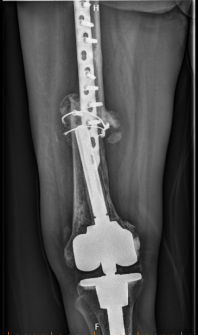

应用3D打印骨整合钛板+cone+定制延长杆行膝关节翻修术。

股骨远端骨缺损严重

3D打印骨整合钛板加强骨折断端增加稳定

翻修术后X线片

术后影像学复查显示,假体位置精准,与术前设计完全吻合。目前患者恢复良好,对手术效果表示非常满意。